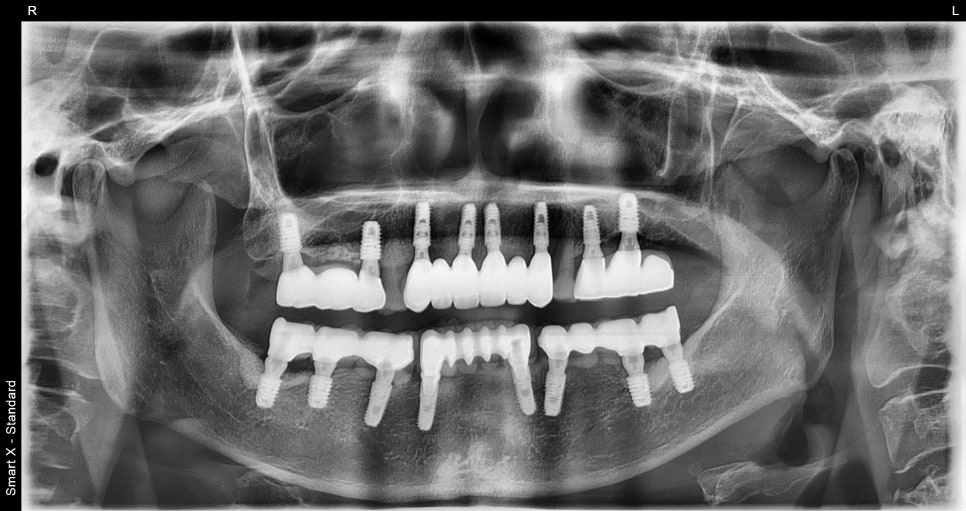

크라운은 언제 올라가요?

임플란트는 식립 후 바로

완성되지 않습니다.

뼈와 임플란트가 결합되는 기간을 거친 후

2차 수술을 통해 잇몸 라인을 형성하게 됩니다.

이 과정은 전치부 임플란트에서 매우 중요합니다.

잇몸 형태가 자연스럽지 않으면

최종 결과가 어색해 보일 수 있기 때문입니다.

임플란트 치과에서는

이 단계에서 잇몸 형태를 정밀하게 조절합니다.

어금니와의 교합까지 고려한 치료

앞니 임플란트는 앞니만 맞춘다고 끝나는 치료가 아닙니다.

어금니 교합까지 함께 맞춰야

전체적인 균형이 유지됩니다.

이번 케이스에서도

어금니 교합 유지

전방유도 조정

전체 교합 균형 개선

이 함께 진행되었습니다.